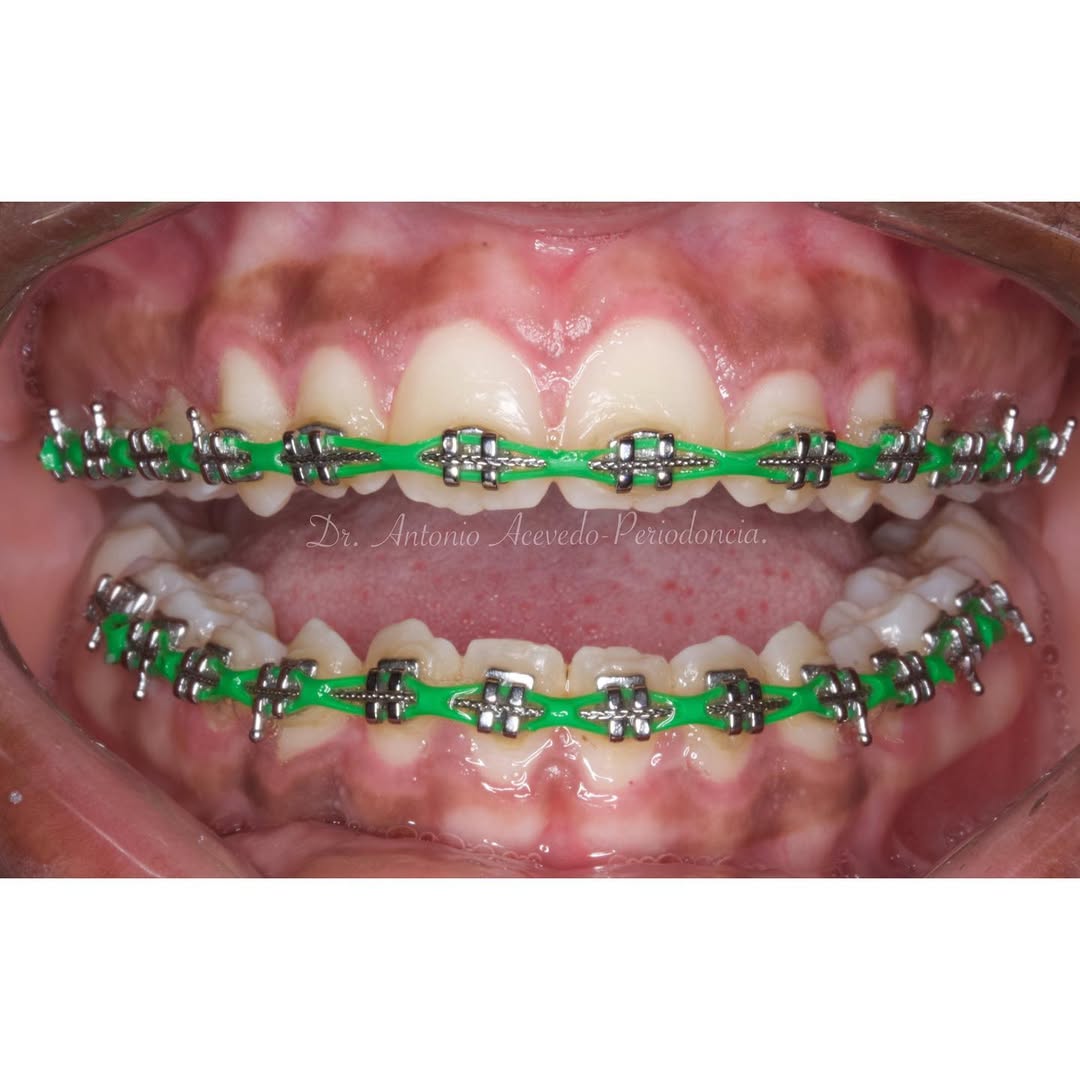

Si quieres dar un salto cualitativo en tu práctica clínica y trabajar con un sistema que realmente optimiza la mecánica ortodóncica, el Curso en Ortodoncia Autoligable con Sistema CCO® de la Universitat Internacional de Catalunya (UIC Barcelona) es una oportunidad para profundizar en un